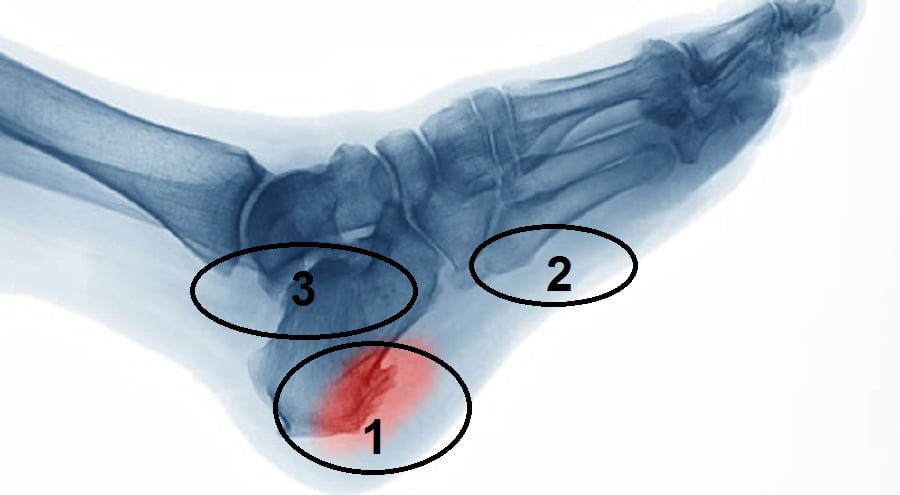

والحكي الصح انو فيه قانون طبي اسمه قانون وولف للشد ....بيقول تنمو العظمه في اتجاه الشد يعني هنالك شد على العظم لذلك نمى وطلع المسمار